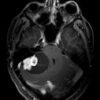

U nguyên bào mạch máu

» Thông tin: Nam giới – 25 tuổi.

» Lâm sàng: Đau đầu + Nôn + Rối loạn thăng bằng.